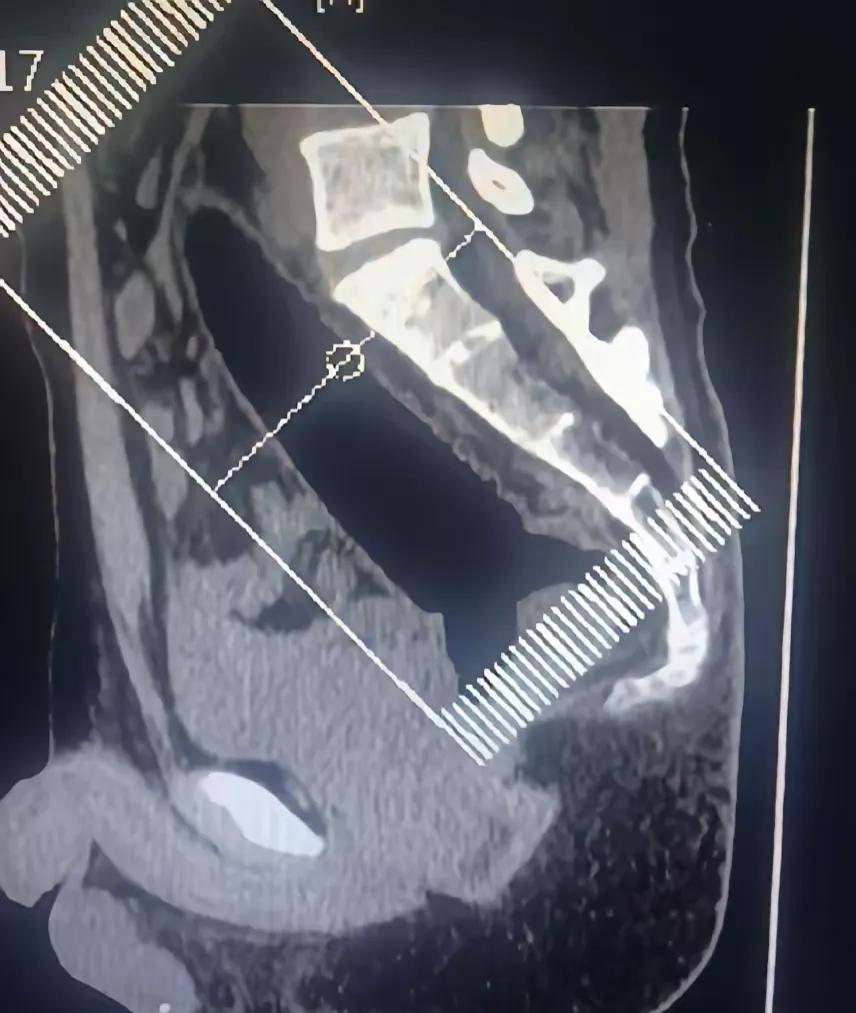

太离谱了!河南郑州,一男子捂着屁股去医院肛肠科看病,可问诊时,男子却扭扭捏捏说屁股卡了一个东西,开始医生还以为问题不大,可看了才发现,这哪是卡了东西,一根异物已深入直肠,最后手术后取出一根22厘米异物。网友:这是个狠人。 接诊的医生回忆,当时男子走进诊室时步子迈得极小,脸憋得通红,手一直死死捂着臀部,问他具体情况,他支支吾吾半天就只说“卡东西了”,问是什么东西,又死活不肯说。医生先安排了CT检查,片子出来的那一刻,在场的医护人员都惊住了——一根长条状的透明异物直直扎在直肠深处,长度看着就不小,边缘还很光滑,根本没法通过常规手法取出来。 没办法,医生只能紧急安排手术。手术室里,医护人员小心翼翼操作,折腾了快一个小时,才把这根22厘米的玻璃制品完整取出来,那东西粗度和普通水杯差不多,光看着都让人觉得后怕。术后男子才吞吞吐吐说,自己是一时好奇才做了这种危险操作,没想到异物进去就出不来了,疼得直冒汗,实在扛不住才敢来医院。 成年人总觉得自己有判断力,可偏偏会因为一时的好奇或荒唐念头,做出伤害身体的事,直肠、肛门这些部位本就脆弱,异物进入不仅可能划伤黏膜导致出血、感染,严重的还会戳破肠道引发腹膜炎,甚至危及生命,这可不是闹着玩的。 更让人无奈的是,这类因异物卡入身体就诊的案例,其实在肛肠科并不少见。有塞瓶盖的、塞电池的,还有塞金属条的,每次接诊,医生都又心疼又无奈。很多人出了事之后,因为觉得尴尬、怕被笑话,会硬扛着不就医,等到实在熬不住了才来医院,往往错过了最佳处理时机,让病情变得更严重,治疗也更复杂。 成年人该对自己的身体负责,更该有基本的安全意识,别让一时的糊涂,给自己的身体和生活都添上不必要的麻烦。 各位读者你们怎么看?欢迎在评论区讨论。